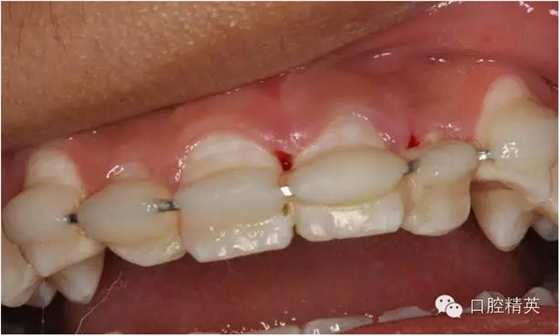

圖1.術(shù)前患者口內(nèi)像、牙槽窩輕度收縮、血凝塊穩(wěn)定、無滲出。

圖1.一周后復(fù)診拆線、唇側(cè)齦乳頭水腫。

圖3.拆線后唇側(cè)觀,牙齦乳頭輕度水腫